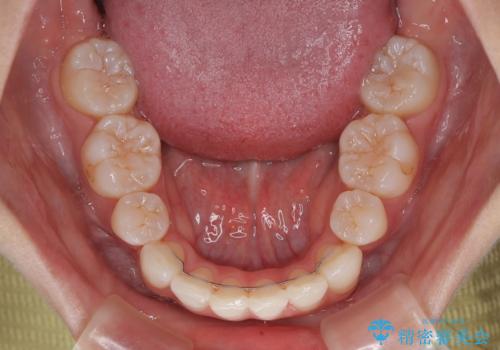

下唇に前歯が当たって跡が残ってしまう状態でしたが、スッキリとした口元に仕上げることができました。